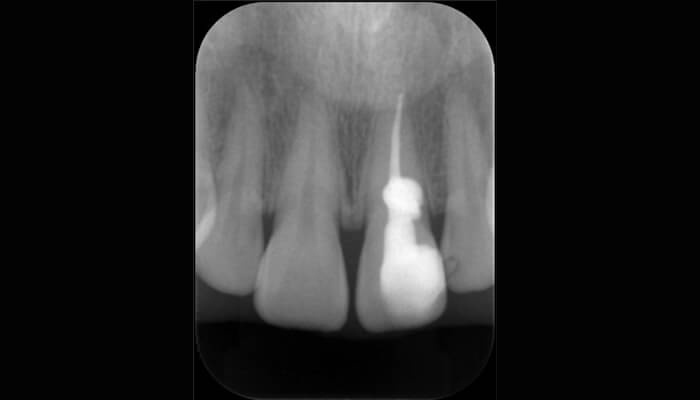

1. 根管が見つからないと、紹介を頂いた左上6のケースです一般的には上顎6番は3根が多いですが、エックス線検査で根があまり離開している様子がみられません。

2.まず、仮封を除去し残っているう蝕を徹底的に除去し、隔壁を形成しました。確かに、根管の数が少ないようです。

3.コーンビームCTで検査しました。根は癒合しており、それに伴い根管も癒合し根尖に向け収束している1根管性の歯でした。2/802程度の出現率と言われる非常に珍しい根管形態でした。

4.根管探索の為の、無用な切削をおこなわずに済みました。根管形成を行い十分な根管洗浄の後に根管充填をおこないました。

5. 術直後のエックス線検査。密な充填がおこなえています。